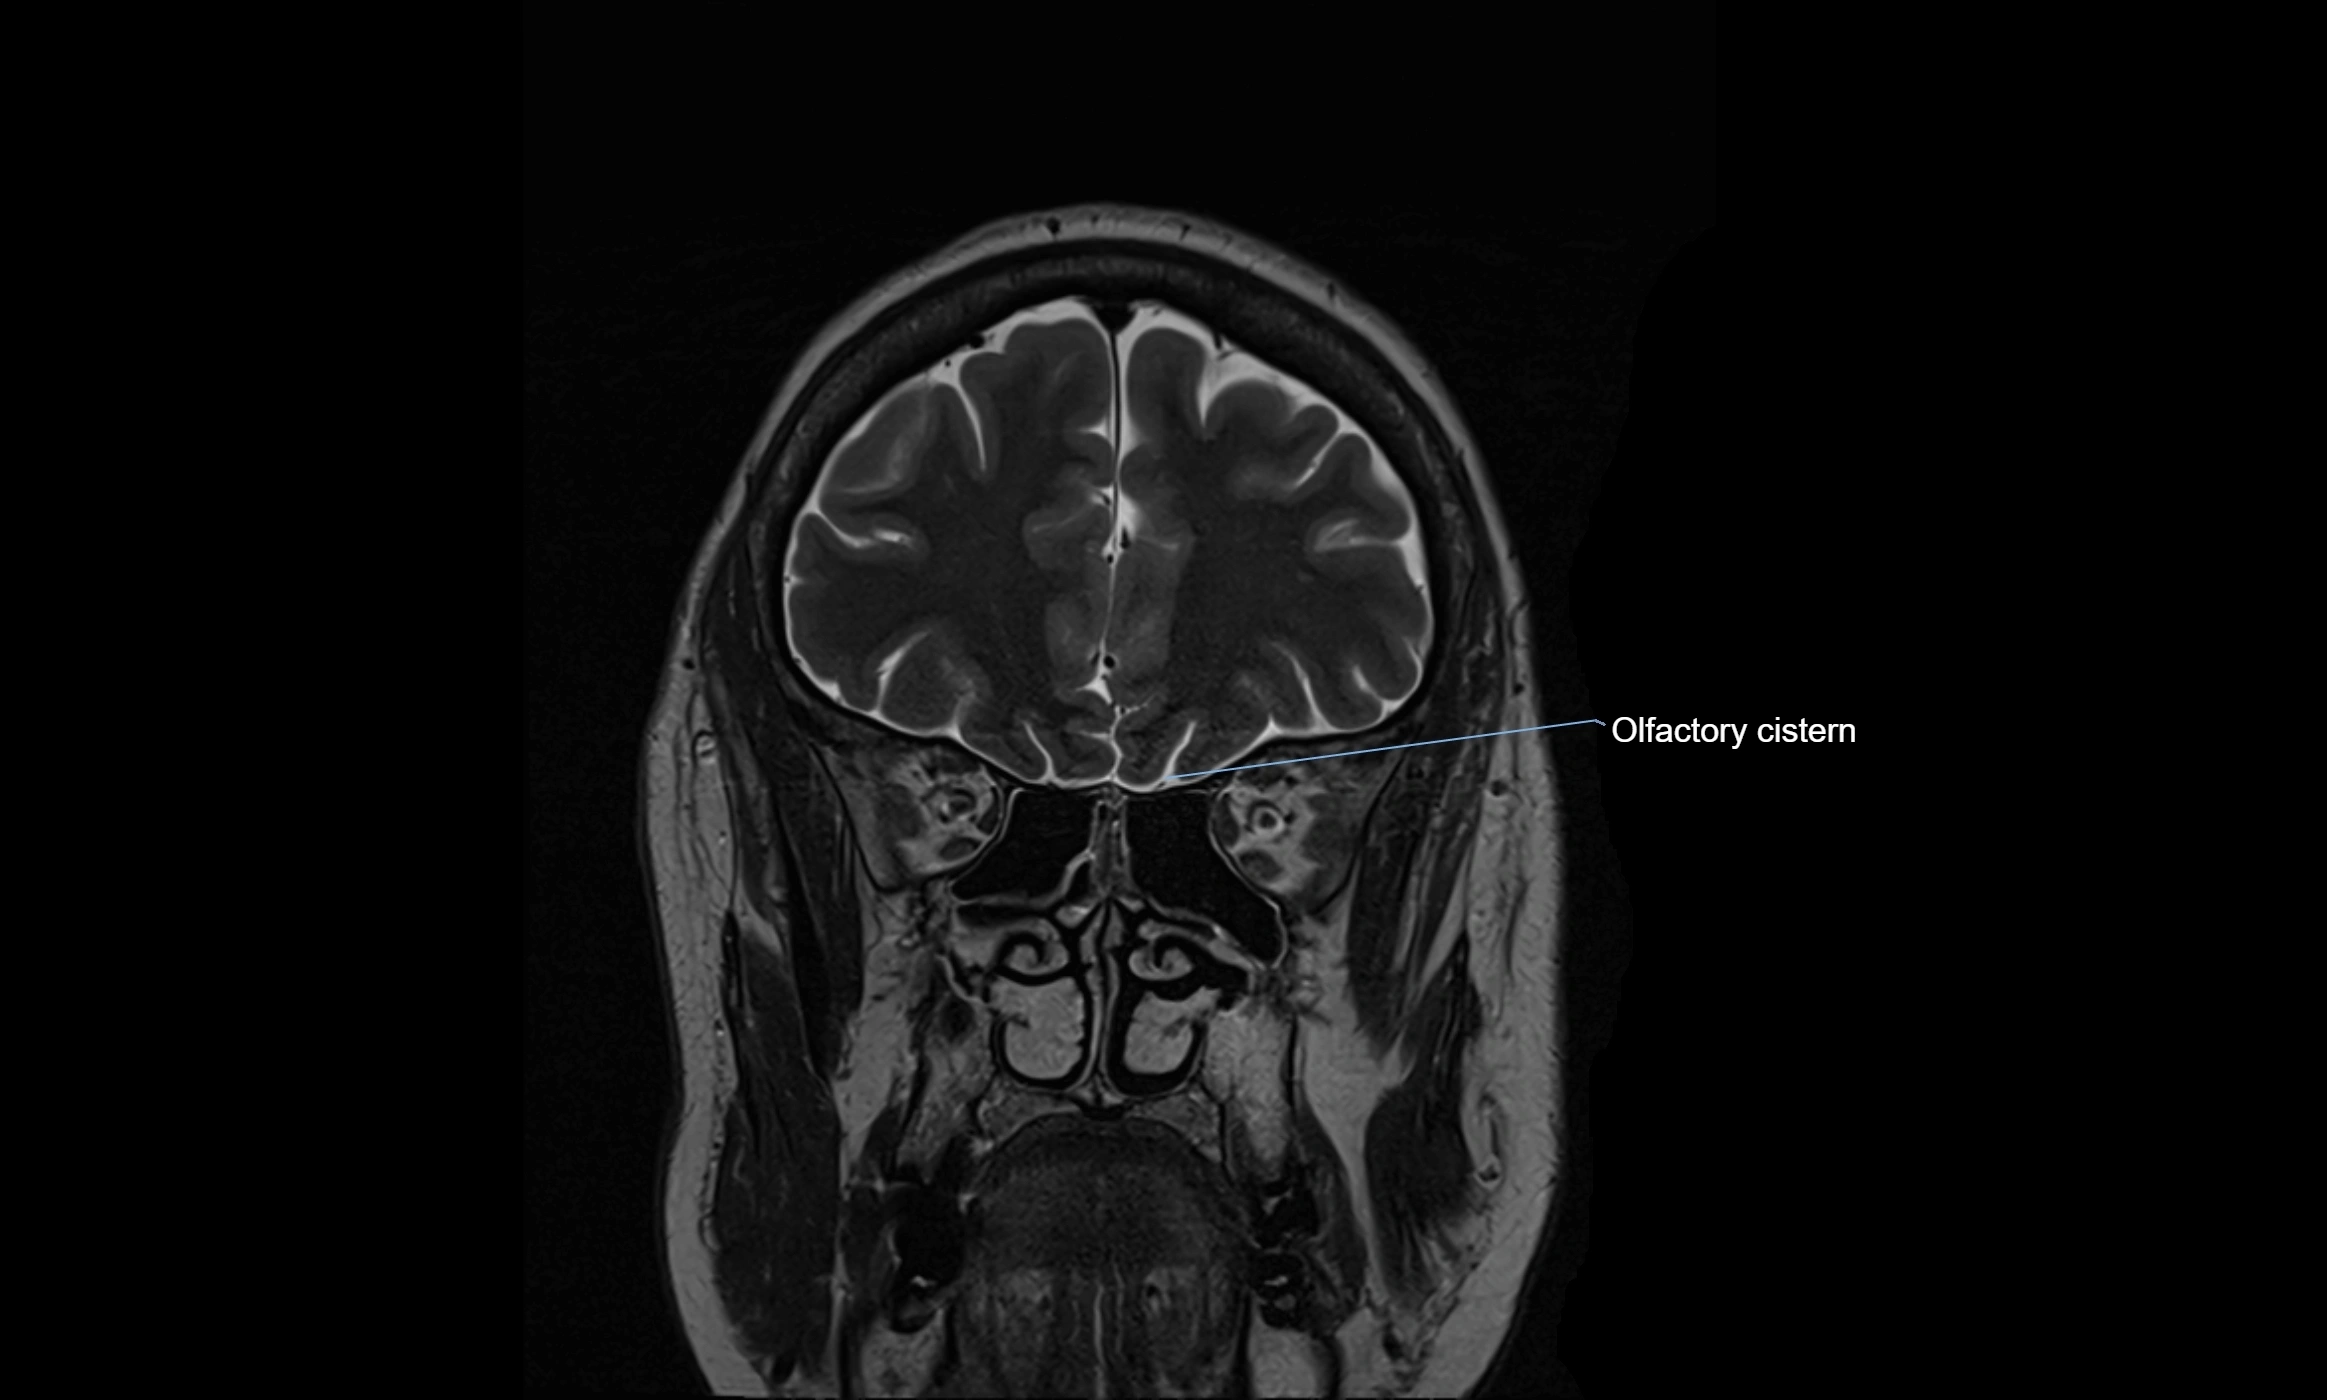

MRI images

image